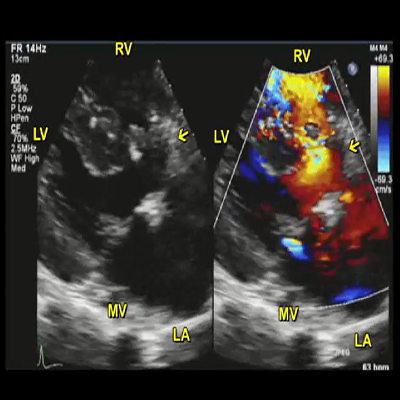

Rheumatic mitral stenosis

Rheumatic mitral stenosis